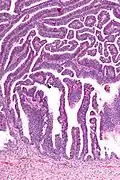

Micrograph of a villoglandular adenocarcinoma the cervix. H&E stain.

The name of the lesion describes it microscopic appearance. It has nipple-like structures with fibrovascular cores (papillae) that are long in relation to their width (villus-like), which are covered with a glandular pseudostratified columnar epithelium.